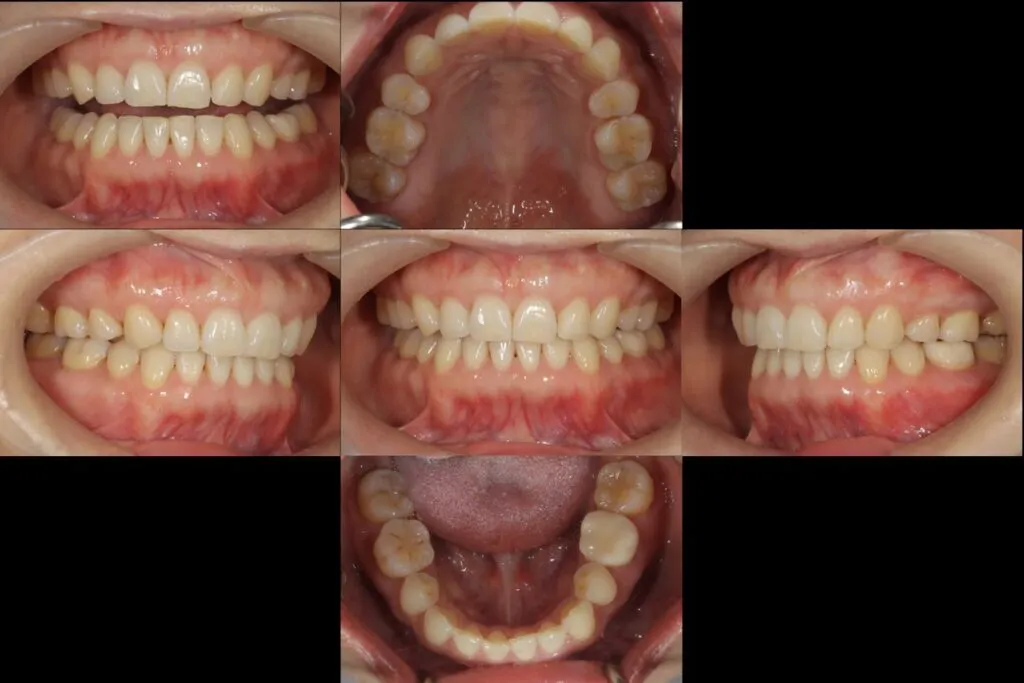

患者様のお悩み | 左下が痛くて噛めない |

|---|---|

治療法・使用素材 | 自費根管治療・補綴処置・オールセラミック |

患者様の年代 | 30代 |

治療開始年齢 | 36歳 |

治療にかかった期間 | 6ヶ月 |

性別 | 女性 |

この治療のリスクについて | 病態が改善しないかもしれない |

治療にかかった費用 | 30万 |

治療前

治療後